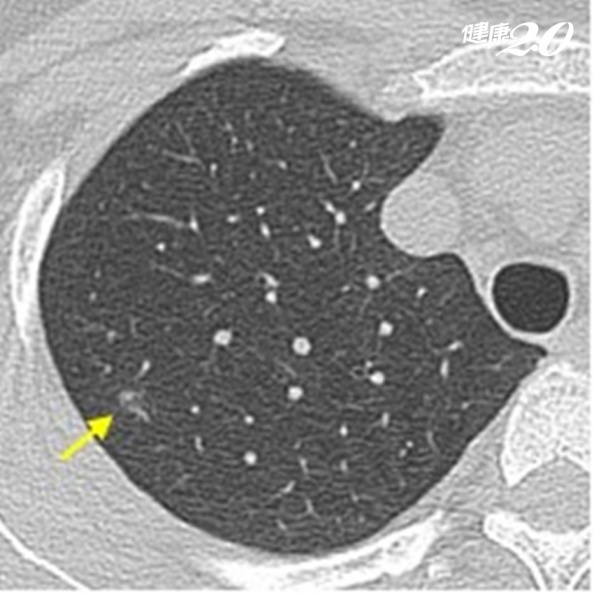

● 病灶型態:醫學對微小肺結節有所謂「毛玻璃狀病灶」,因在斷層掃瞄影像下,這類肺結節的邊緣或內部呈現不規則,霧霧的、像棉花狀,猶如一片毛玻璃擋在肺組織前面,其密度也會輕微增加。若為邊緣明確且內部呈現實心狀態的就稱為實質肺結節或腫瘤。

▲在斷層掃瞄影像下,結節呈現邊緣不規則,霧霧的、像棉花狀,稱為毛玻璃狀病灶(GGO)。